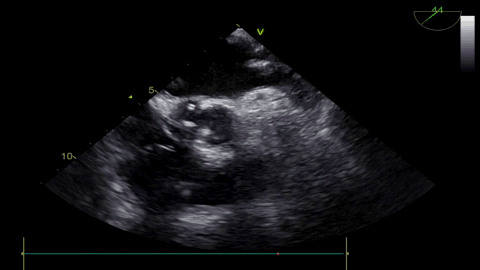

术前超声:

球扩后超声

发生瓣叶切割,无窦侧瓣叶切割,Type0结构形变为类三叶瓣结构。

超声显示人工瓣膜工作良好,微量瓣周漏,术后一周顺利出院,术后随访无并发症,恢复良好。